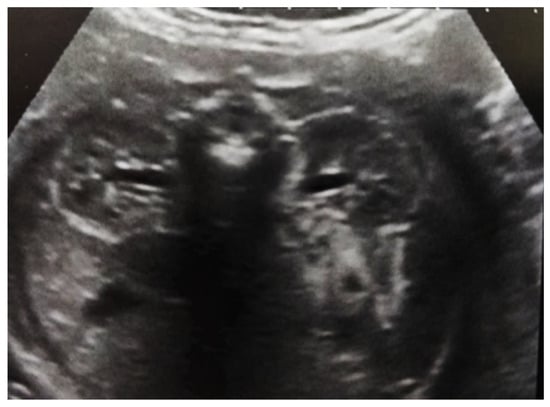

Our experience with congenital malformations of the urinary system refers to the following clinical case (Figure 2, Figure 3, Figure 4, Figure 5, Figure 6, Figure 7, Figure 8 and Figure 9). In the first case, during pregnancy, the 21-week ultrasound determined bilateral renal pyelectasia. The fetus had hydronephrosis on the right; at 31 weeks, it had bilateral hydrocalconephrosis; and at 32 weeks, bilateral pyelectasia. It suffered premature birth at 36 weeks, with complicated anomalies of the forces of contraction, prolonged birth, and birth weight of 2200 g. Postnatal ultrasonography was supplemented by intravenous urography, and bilateral hydronephrosis was determined. Hydrocalconephrosis on the left was discovered. The complete diagnosis was established: congenital renal malformation; bilateral pyelectasia; bilateral hydronephrosis; hydrocalconephrosis on the left; and severe reduced glomerular filtration rate (GFR), GFR > 2SD below mean.

Figure 5. Ultrasound at 32 weeks of gestation. Bilateral pyelectasis.